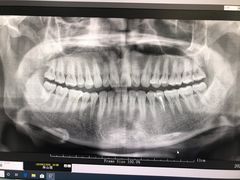

• 牙博士口腔品牌连锁(杨浦店)

• -牙博士口腔品牌连锁(杨浦店)

haibaraeva | 21-01-26